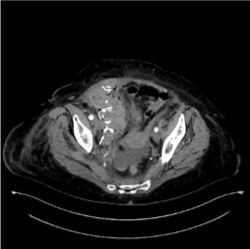

The patient was stabilized and abdominal CT revealed a large hematoma of the right rectus sheath with arterial exavascation from a branch of the right inferior epigastric artery (Figure 1).

Figure 1. Inferior epigastric artery, Arterial blushing.

As a conclusion we want to stress out that the spontaneous rectus sheath hematoma (Figure 2) is a condition that can mimic acute abdomen and the gold standard examination for depicting such a condition is CT scan with IV contrast median. Conservative approach in most cases is sufficient and the condition is self limited (Figures 3,4 and 5). If the conservative approach fails vascular embolization or surgical repair is indicated [1-3].

Figure 2. Rectus sheath hematoma.